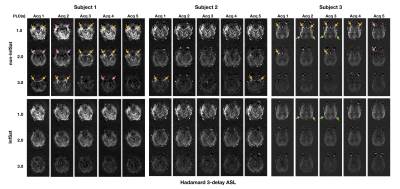

Figure 2. Perfusion weighted images from HASL acquired without (top row) and with (bottom row) inflow saturation (InfSat). A single slice acquisition is shown for each of 3 PLDs in 3 subjects. High signal (yellow arrows) and low signal (pink arrows) intravascular artifacts were observed in 80% of all acquisitions in the three subjects. High intravascular signal fluctuating across PLDs was either eliminated or greatly reduced with inflow saturation. However, stable artifacts (green arrows) in the distal middle cerebral artery were not suppressed by inflow saturation.